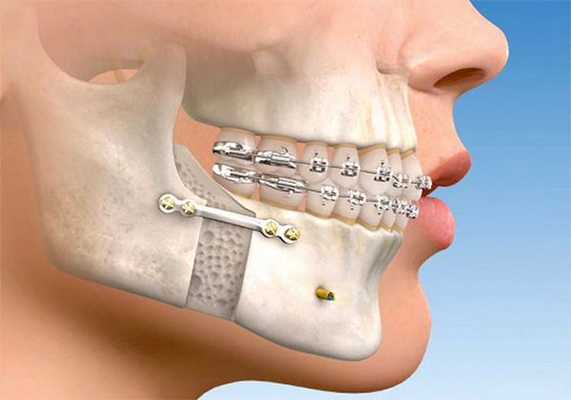

Хирургические этапы лечения включают: применение компрессионно-дистракционного остеогенеза, эндопротезирование ВНЧС, реконструктивные операции: остеотомия верхней и нежней челюсти, пластические операции.

От ортодонтов зависит качественное смыкание зубных рядов после выполнения челюстно-лицевой операции и окончательный результат комплексного лечения. Хирурги же перемещают челюсти (одну или обе) и изменяют их форму в случае необходимости. После перемещения челю сти они придают ей правильное положение и закрепляют специальными фиксирующими элементами. Для скрепления используют специальные пластины из медицинского титана. В некоторых случаях для небольшой коррекции контуров лица (подбородка, скул, углов нижней челюсти) используются имплантаты.

Такой вид хирургии требует детального планирования. Операция проводится в условиях наркоза из внутриротового доступа [20] . После неё пациент наблюдается в стационаре в течение 1-2 дней [21] . При полном сращении челюстных костей (примерно через 14 недель) ортодонт заканчивает выравнивание зубов с применением брекет-системы.